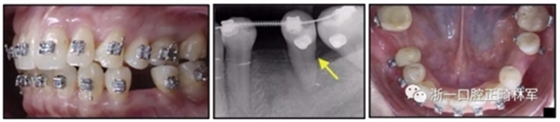

36歲;女性;尋求下頜左后方區(qū)域間隙管理的建議(圖1和圖2),通過治療獲得了良好的牙頜面效果(圖3和圖4)。她被診斷患有骨性I類和代償性牙性II類錯合畸形,并且上頜左側尖牙缺失(圖1和2)。大約七年前,由于不可修復的齲齒,拔除了下頜左側第一和第二磨牙(圖5)。37相鄰的第三磨牙向近中移動并傾斜入間隙,導致無牙頜間隙減小至約14 mm(圖2和圖5)。臨床和影像學評估顯示多發(fā)性齲損和在下頜右側567處有一不良的固定橋修復體(圖1和5)。此外,下頜左中切牙缺失,造成下頜中線向左側偏移約3 mm(圖1和圖2)?;颊咦栽V,她的右上第一前磨牙和左上尖牙在13歲時由其家庭牙醫(yī)拔除,因為它們被阻塞到頰側萌出(圖1)。上頜第二磨牙缺失(未知病因),并且相鄰的第三磨牙已經(jīng)轉移到第二磨牙間隙中。如補充材料所示,美國正畸學差異指數(shù)DI是28分。種植體部位(下頜左側和右側第一磨牙)由于復雜性得到額外4分(補充材料)。

圖1. 治療前面部和口內(nèi)照片

圖5. 治療前的側位片(上圖)和全景(下圖)的X光片